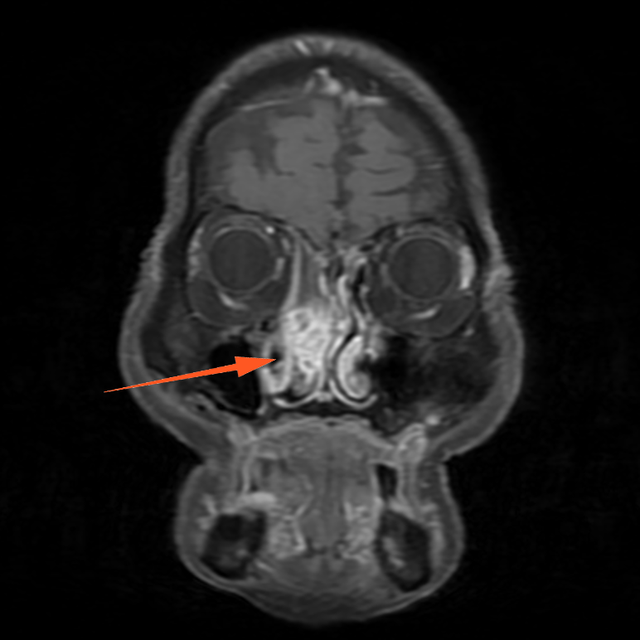

进一步增强MR显示:鼻腔右侧异常信号影,T1等信号,T2等高信号,DWI高信号,增强后周边强化为主。

蒋主任仔细阅读影像学图像,该患者的肿物在T2相有 “脑回征”,但又不典型,鼻窦骨质也没有明显的增生,肿物已经占满整个右侧额窦窦腔,好在患者额窦气化尚可,肿物未越过瞳孔中线,要彻底清除肿物,需要打开额窦,将窦内软组织完全清理干净并磨除基底部部分骨质再烧灼。